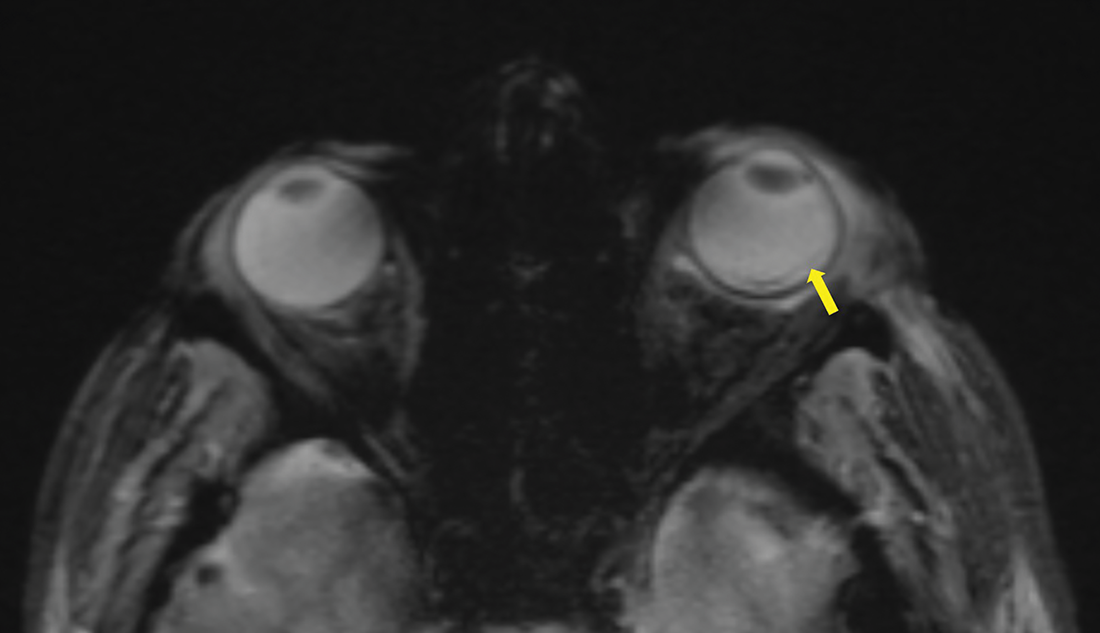

Figure 3

Axial T2 gradient echo sequence showing a retinal detachment with a slight linear hypoT2 signal (arrow).